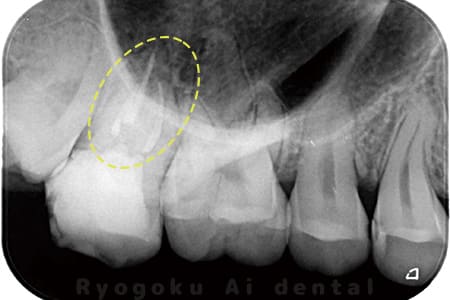

根管内の異物

- 原因

- 根管内異物(ファイル破折)による慢性根尖性歯周炎

- 治療期間

- 3ヶ月

- 治療内容

- マイクロスコープを使用した根管内異物除去並びにマイクロエンド

- 治療費用

- 121,000円(ファイル除去費用も込み)

他院で細い器具(ファイル)が根管内に破折した状態で、咬合痛を主訴に来院された患者様です。ファイルをマイクロスコープ下で除去し、根管治療を行ないました。